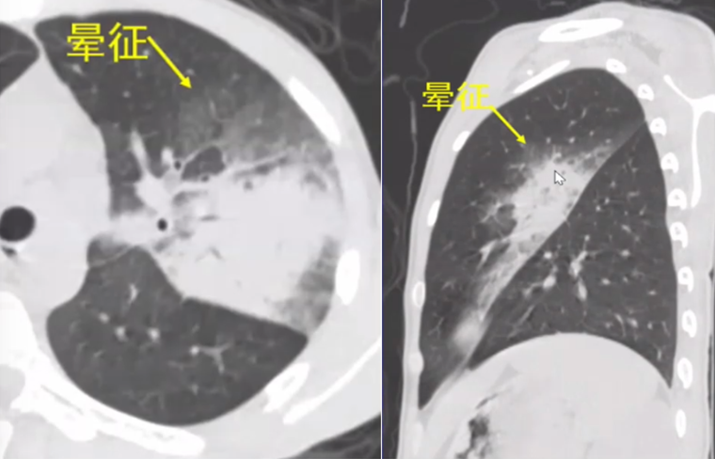

(2)曲霉容易侵犯血管,并在血管周围产生“晕征”(图9)

图片

图9  晕征

图13可见大片实变周边围绕着磨玻璃影,磨玻璃影是出血表现,说明血管被破坏,这也意味着病变侵犯血管,因此出现了晕征。在矢状面可以发现,晕征围绕着病灶实变,因为实变周边的血管非常丰富,毛细血管较粗,曲霉侵犯实变周边的血管后导致局部毛细血管中的血液破裂到了周边,因此,晕征一定在实变周边。

图13  曲霉感染表现—晕征